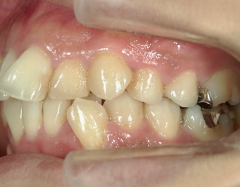

矯正歯科 治療前矯正歯科 治療前

矯正歯科 治療前 上下左右4番 計4本を抜歯して叢生を改善しました。

no.31_1962_治療前_右.JPGno.31_1962_治療前_正面.JPGno.31_1962_治療前_左.JPG